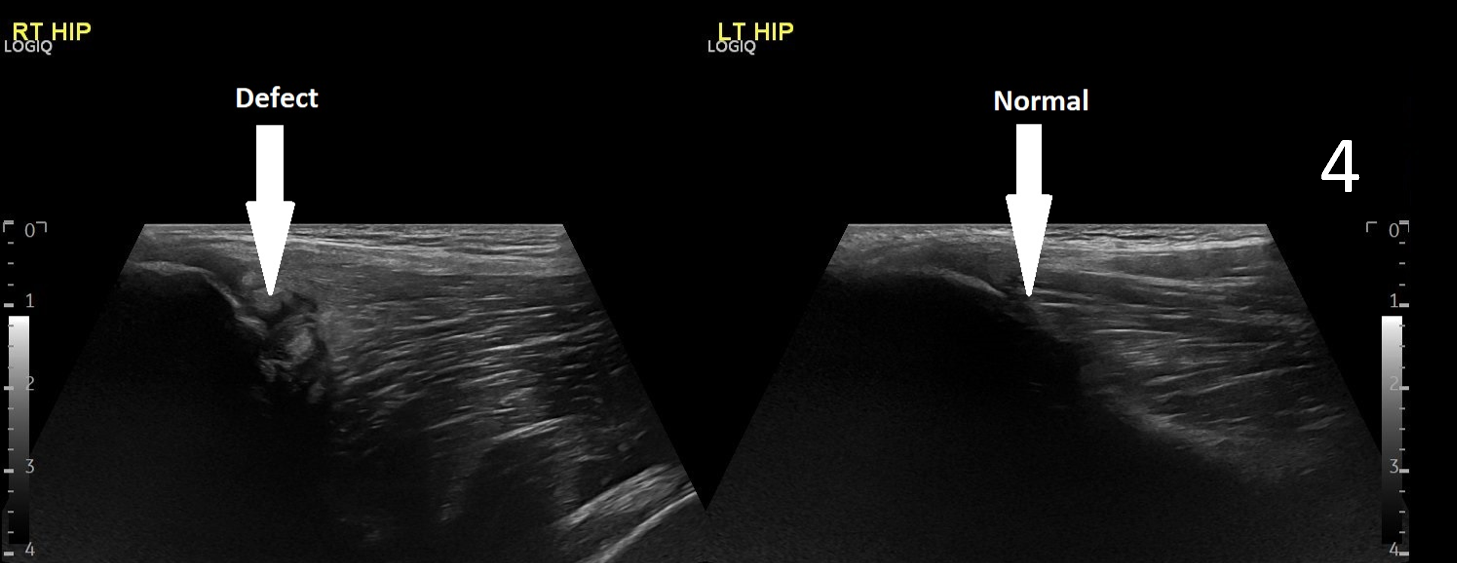

The patient was focally tender in the right iliac fossa at the level of the anterior superior iliac spine (ASIS). At this site, there was muscle fibre disruption and a haematoma at the insertion of the sartorius tendon with minimal retraction (Figure 2). There was cortical irregularity at the ASIS and a bony fragment within the retracted tendon and also neovascularisation here on power Doppler (Figure 3). On comparison to the contralateral side, there was altered architecture of the sartorius muscle with a clear defect while the left side looked normal (Image 4). Ultrasound appearances in keeping with a sartorius tendon avulsion. This was treated conservatively with rest, analgesia and a return to normal activities after two months. Surgical interventions are uncommon and are reserved for when the fracture fragment has migrated more than 3cm.